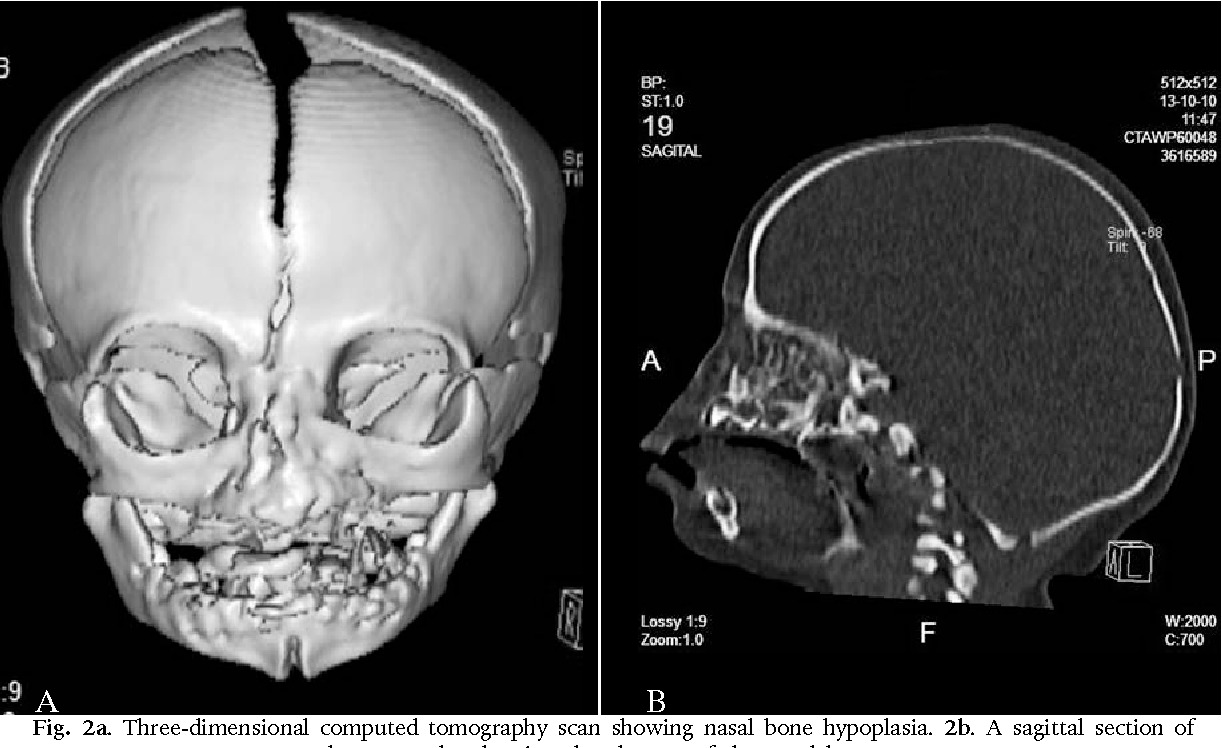

وتُعرف الحالة التي وُلدت بها الطفلة باسم انعدام الأنف الخلقي أو Arhinia، وهي من التشوهات الخلقية شديدة الندرة على مستوى العالم، حيث يولد الطفل دون أنف خارجي أو ممرات أنفية، ما يؤثر بشكل مباشر على عملية التنفس، وفقًا لما ذكرته بيانات معهد الصحة الأمريكية (NCBI).

وتحدث هذه الحالة نتيجة خلل في تكون الوجه خلال الأسابيع الأولى من الحمل، تحديدًا بين الأسبوع الثالث والثامن، وهي المرحلة المسؤولة عن تشكيل ملامح الوجه والأنف، وفي بعض الأحيان تكون مرتبطة بتشوهات أخرى في منتصف الوجه، مثل تباعد العينين أو مشكلات في الحنك والأذن.

ويمكن اكتشاف هذا التشوه قبل الولادة من خلال الفحوصات الدقيقة، مثل الموجات فوق الصوتية أو التصوير بالرنين المغناطيسي، إلا أن بعض الحالات لا يتم رصدها إلا في مراحل متأخرة من الحمل.